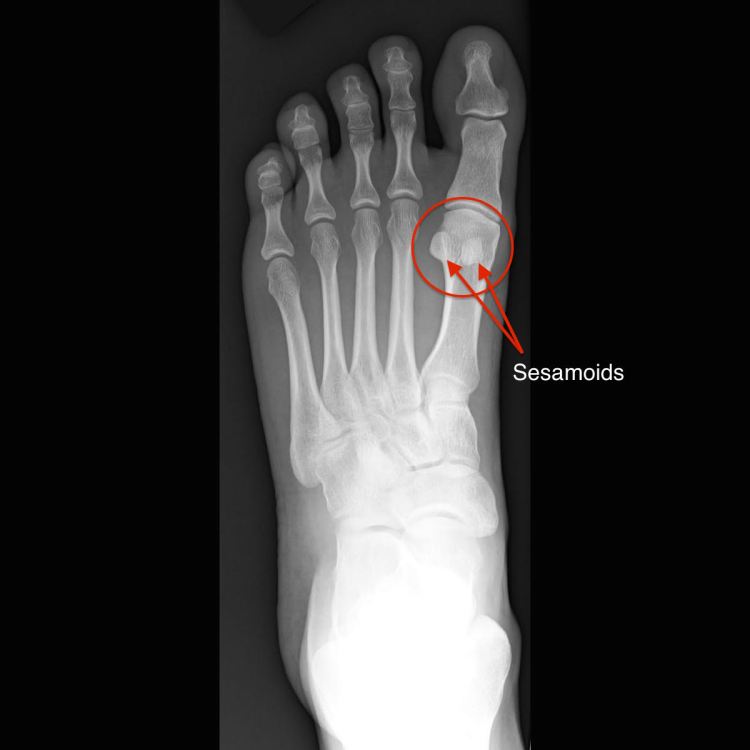

Sports Injuries of the Foot and Ankle Discussions of common sports injuries of the foot and ankle, including sport-specific injuries. Basketball Injuries Football Injuries Baseball Injuries Golf Pinched Nerve Sesamoiditis Share this: Share on X (Opens in new window) X Share on Facebook (Opens in new window) Facebook Like Loading...